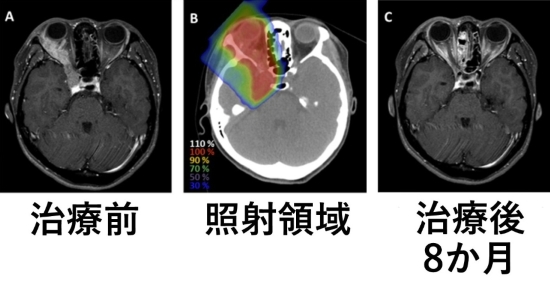

右眼窩外側から頭蓋内に進展する涙腺がんに重粒子線治療57.6 Gy/16回を行いました。

治療後腫瘍は消失し、8か月が経過しておりますが再発を認めておりません。

(注)Gyは生物学的効果比加重線量です。